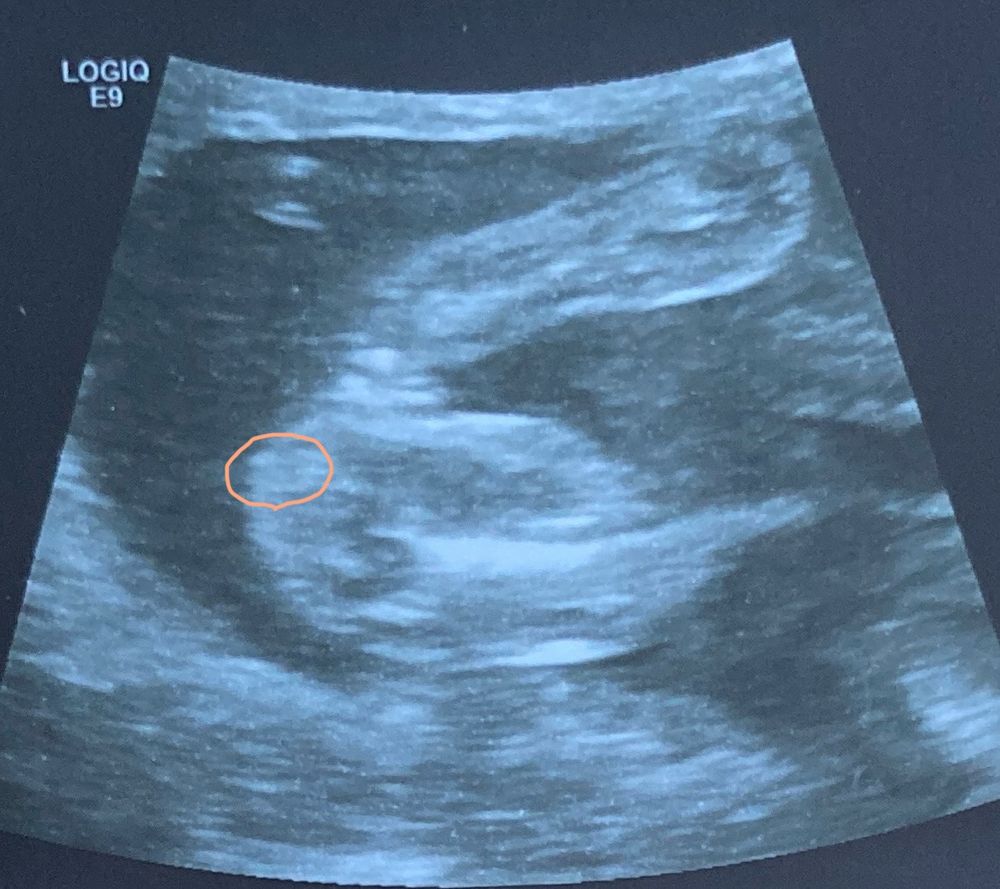

Определение Пола по фото узи

Мальчик мне кажется

Галина, что-то как-то размыто.... Я вот в 14 недель увидела и срущу поняла что девочка. Моя не стеснялась села так что всё было видно. Но вроде мальчик... Вообще рано говорить об этом ведь ещё органы половые не до конца сформировались.... Вот у меня с сыном только на 23 недели смогли сказать кто точно, а с дочкой уже в 11 недель сказали что девочка. Главное чтобы был самый счастливый и здоровый. Лёгких родов и здоровья вам)

Галина, ну я смотрю похожа на девочку, но слишком длинный наверное пальчик... У меня вообще подружка ходила и всё говорили девочка а родила мальчика, хорошо что сама родила и показали что мальчик а то не поверила бы. Размеры разные бывают поэтому.... Мне кажется мальчик просто неверное только всё начало формировать. А вообще прислушайтесь к себе. Ведь мы же в глубине души знаем кто. Я вот 1Б хотела девочка и говорила что девочка наверное, но что-то внутри мне говорил что мальчик и в 2Б думала мальчик всё так думали, но я чувствовала что девочка. Главное услышать этот голос) А вообще конечно не понятно кто... Но пальчики на ножке хорошо видно, такие сладкие) ой, как я скучаю по животику ( хотя только 4 месяца прошло.... Хотя я ходила с 1б- 42 недели 2б- 43 недели..... Долго его мне хотелось ещё как можно дольше ходить!

Камилла , мне кажется вот половые губы, сейчас только увеличила и увидела. Видно половые губы и посередине разделение, ну то есть если была бы машонка, то было бы полноценно круглое, а тут прям разделение, ну это я так вижу, а там не знаю🤔 У нас просто пол ребенка бесплатно никто не говорит, принести фотку и попросить посмотреть я не смогу, нужно платить🤦🏼‍♀️ Изображение

На фото нижнем у ребенка вообще не вошло в кадр то место, по которому опрелеляют пол. А верхнее фото... Я не поняла, какая это часть тела...